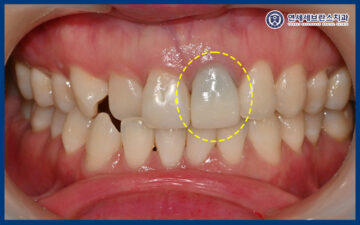

<초진 시 보이는 변색>

위 환자분께서는 오래전

앞니에 신경치료를 받았었는데

해당 앞니에 변색이 있고 뿌리 끝 염증이 있어

정기검진이 필요하다는 소견을 들으셨었습니다.

첫 내원 당시에는 치아 색상이

심미적으로 아쉬운 상태였지만

뿌리 끝 염증으로 인한 통증이나

일상생활의 불편감은 크지 않아

우선 경과를 지켜보는 상황이었는데요.

25.12.22

<2개월 뒤 생겨난 잇몸 뾰루지>

두 달 뒤 잇몸 뾰루지가 생겼는데